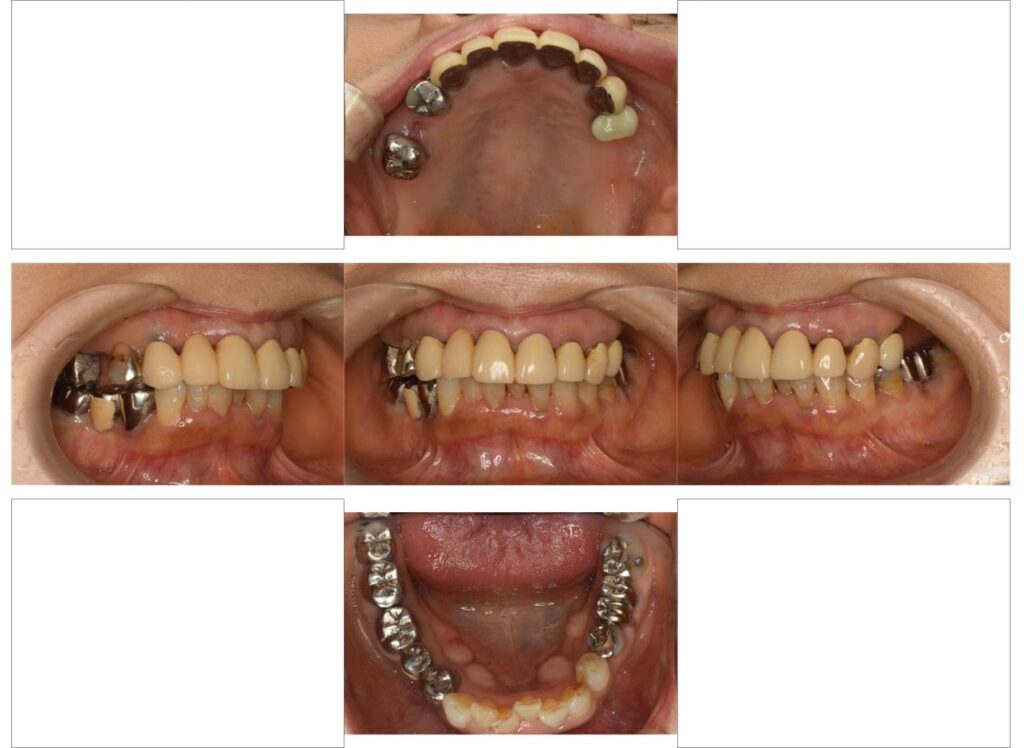

上の奥歯(上顎大臼歯)の2本がない口腔内

口腔内写真を撮影します。

処置前の状態を記録することは治療前、治療中、治療後にも非常に重要な役割を果たします。

今回ご紹介させていただいた症例は他の歯にも問題があり、噛み合わせが不安定な方でした。

治療前からその必要性をご説明させていただき治療を同時に進行いたしておりました。

全顎的な治療になりましたのでその他の歯の治療に関しては今回は割愛させていただきます。

インプラント治療後の口腔内写真